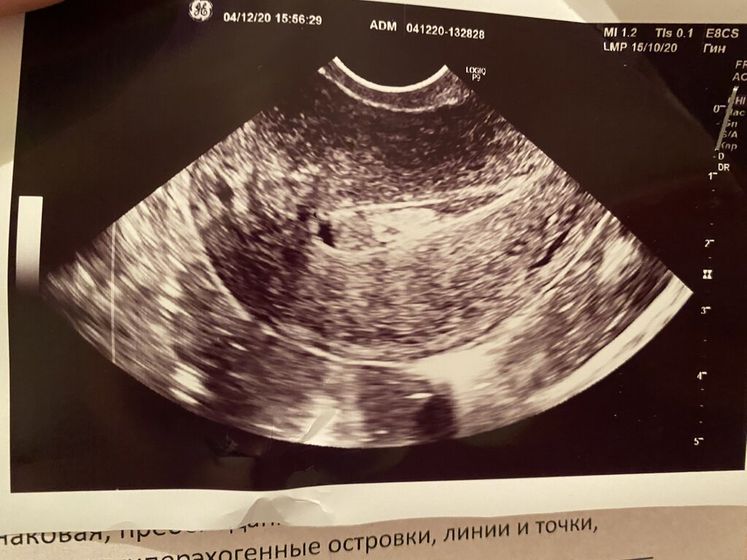

Ниже прикрепляю УЗИ.

А на снимке как будто ребеночек прикрепился?

Я сама не знаю, что это на снимке такое ?

Вроде как какое-то образование, может полип или ещё что, самой толком ничего не объяснили ??♀️

Сейчас была у врача, та сначала тоже беременность предположила, но из-за крови в полости матки не могут точно сказать, что это + тесты на беременность отрицательные

Ещё врач и УЗИст сказали мне, что картина у меня, как после аборта или выкидыша ? сами в общем причину не знают